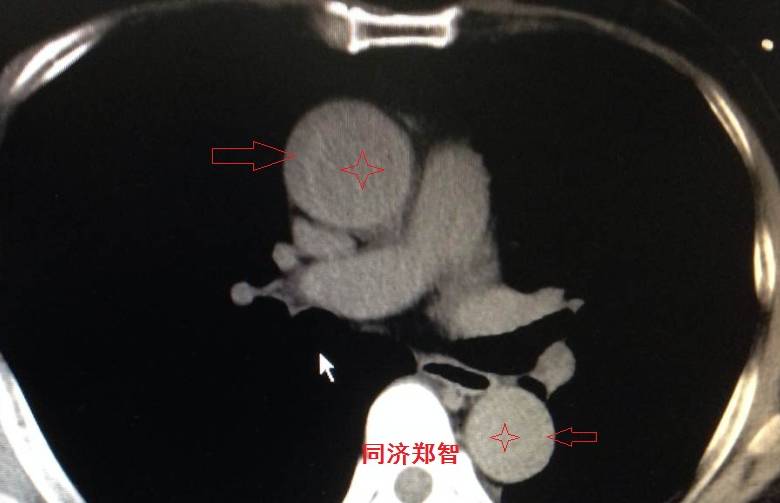

病例二

胸部平扫CT提示升主动脉增宽(红色星形标记),CTA证实A型主动脉夹层伴升主动脉夹层动脉瘤形成。